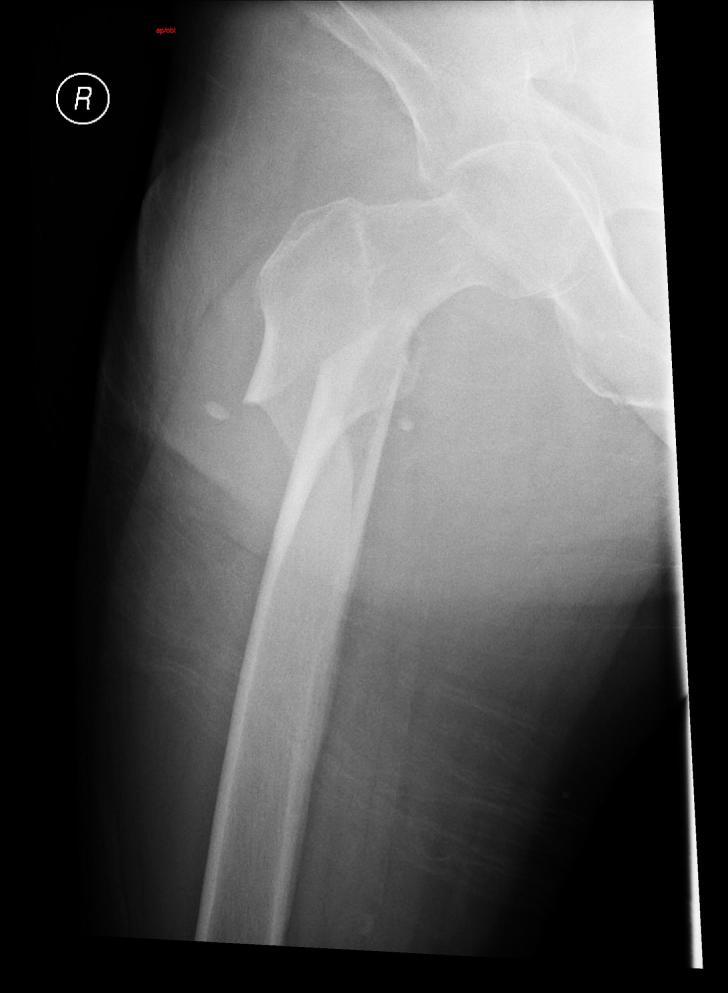

The Segway® self-balancing personal transporter has been used as a means of transport for sightseeing tourists, military, police and emergency medical personnel. Only recently have reports been published about serious injuries that have been sustained while operating this device. This case describes a 67-year-old male who sustained an oblique fracture of the shaft of the femur while using the Segway® for transportation around his community. We also present a review of the literature.

赛格威(Segway®)自平衡个人运输工具已被用作观光游客、军队、警察和紧急医疗人员的交通工具。直到最近才有关于操作该设备时遭受重伤的报道发表。本病例描述了一名67岁男性,他在社区内使用赛格威(Segway®)进行交通出行时,股骨干发生了斜形骨折。我们还对相关文献进行了综述。